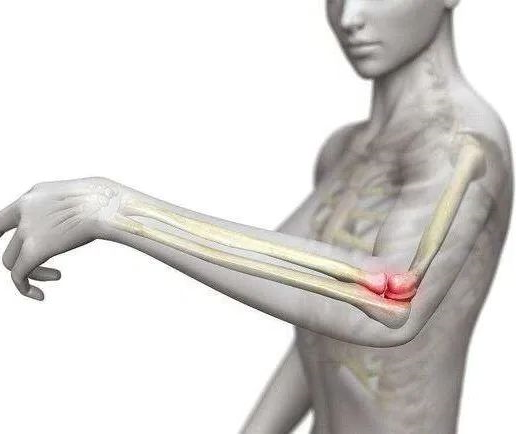

肱骨外上髁炎

肱骨外上髁炎是一种发生于肱骨外上髁处,伸肌总腱起点附近的慢性损伤性炎症,总称为肱骨外上髁炎。其受累结构包括骨膜、肌腱、关节滑膜等,而骨质并无实质性损害。网球运动员易发此种损伤,故俗称“网球肘”。ESWT 治疗肱骨外上髁炎的有效率为68%~91%。

肱骨内上髁炎

肱骨内上髁炎是一种发生于肱骨内上髁处,前臂曲肌肌总腱起点的慢性损伤性炎症,总称为肱骨内上髁炎。其受累结构包括骨膜、肌腱、关节滑膜等,而骨质并无实质性损害。高尔夫运动员易发此种损伤,故俗称“高尔夫球肘”。ESWT 治疗肱骨内上髁炎的有效率为~91%。